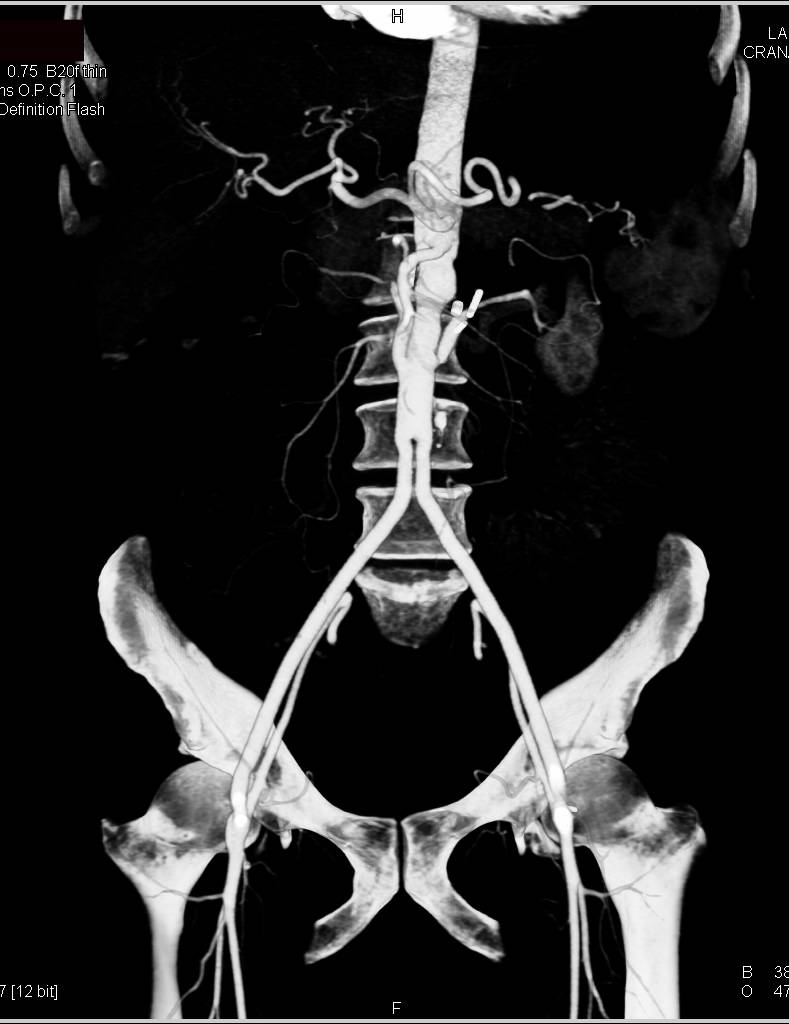

Runoff with Peripheral Vascular Disease and Artifact off a Total Hip Replacement (THR)